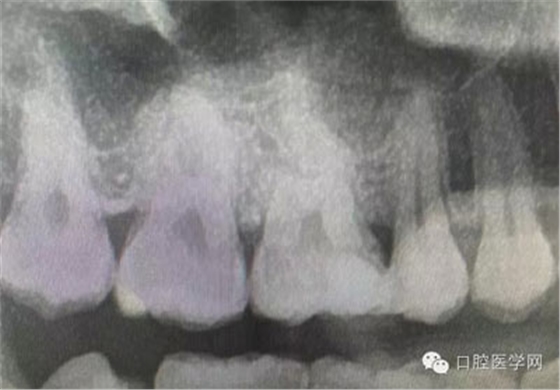

深齲或者是齲壞備洞的時(shí)候意外穿髓,我們?cè)趺刺幚砗眯??后期出現(xiàn)的牙髓的癥狀,是我們操作的問題?比如細(xì)菌層的存在,我們沒有清理干凈?還是我們窩洞沒有進(jìn)行消毒,或者是隔濕沒有做好導(dǎo)致的粘結(jié)出現(xiàn)問題,還是材料充填的時(shí)手法不對(duì),導(dǎo)致的材料收縮過大,還是我們的光照設(shè)備出現(xiàn)了老化沒有完全達(dá)到想要的固化,還是懸空的釉質(zhì)沒有去除導(dǎo)致的微滲漏的發(fā)生,或者是材料本身對(duì)牙髓產(chǎn)生的刺激,還是材料選擇的問題,或者是我們對(duì)材料的性能和說明沒有足夠的了解導(dǎo)致的,沒有按照材料的要求去做,還是我們自身對(duì)牙齒情況的判斷出現(xiàn)的問題......

這是一例外院樹脂修復(fù)后十個(gè)月出現(xiàn)牙髓炎癥狀的患者。遇到這樣子的患者大家會(huì)怎么做,證明選擇,還有就是可做可不做治療的如何去平衡。